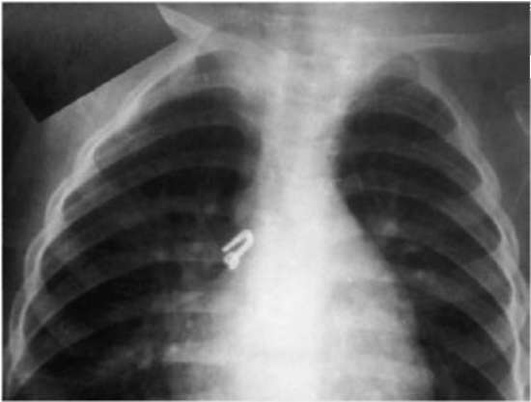

В случае внезапного появления кашля, в том числе спастического, без признаков ОРИ, следует подумать и об инородном теле в дыхательных путях, особенно у ребенка, ранее не имевшего спастического кашля (рис. 16.3). В этом случае характерен приступ коклюшеподобного кашля - навязчивого, но не сопровождающегося репризами. Такой кашель может длиться непродолжительное время, при продвижении инородного тела в более мелкие бронхи кашель может прекратиться.

pic 0064

Рисунок 16.3Инородное тело в правом главном бронхе

Несмотря на типичную картину и анамнестические данные, до сих пор ранняя диагностика аспирации инородного тела на практике вызывает затруднения. Только у 32% детей раннего возраста инородные тела выявляли в 1-е сутки. У большей части пациентов (51,6%) их выявляли в срок позднее месяца, и основным симптомом у этой группы детей был кашель. Следует иметь в виду, что отсутствие изменений на рентгенограмме легких не может полностью исключить данную патологию.